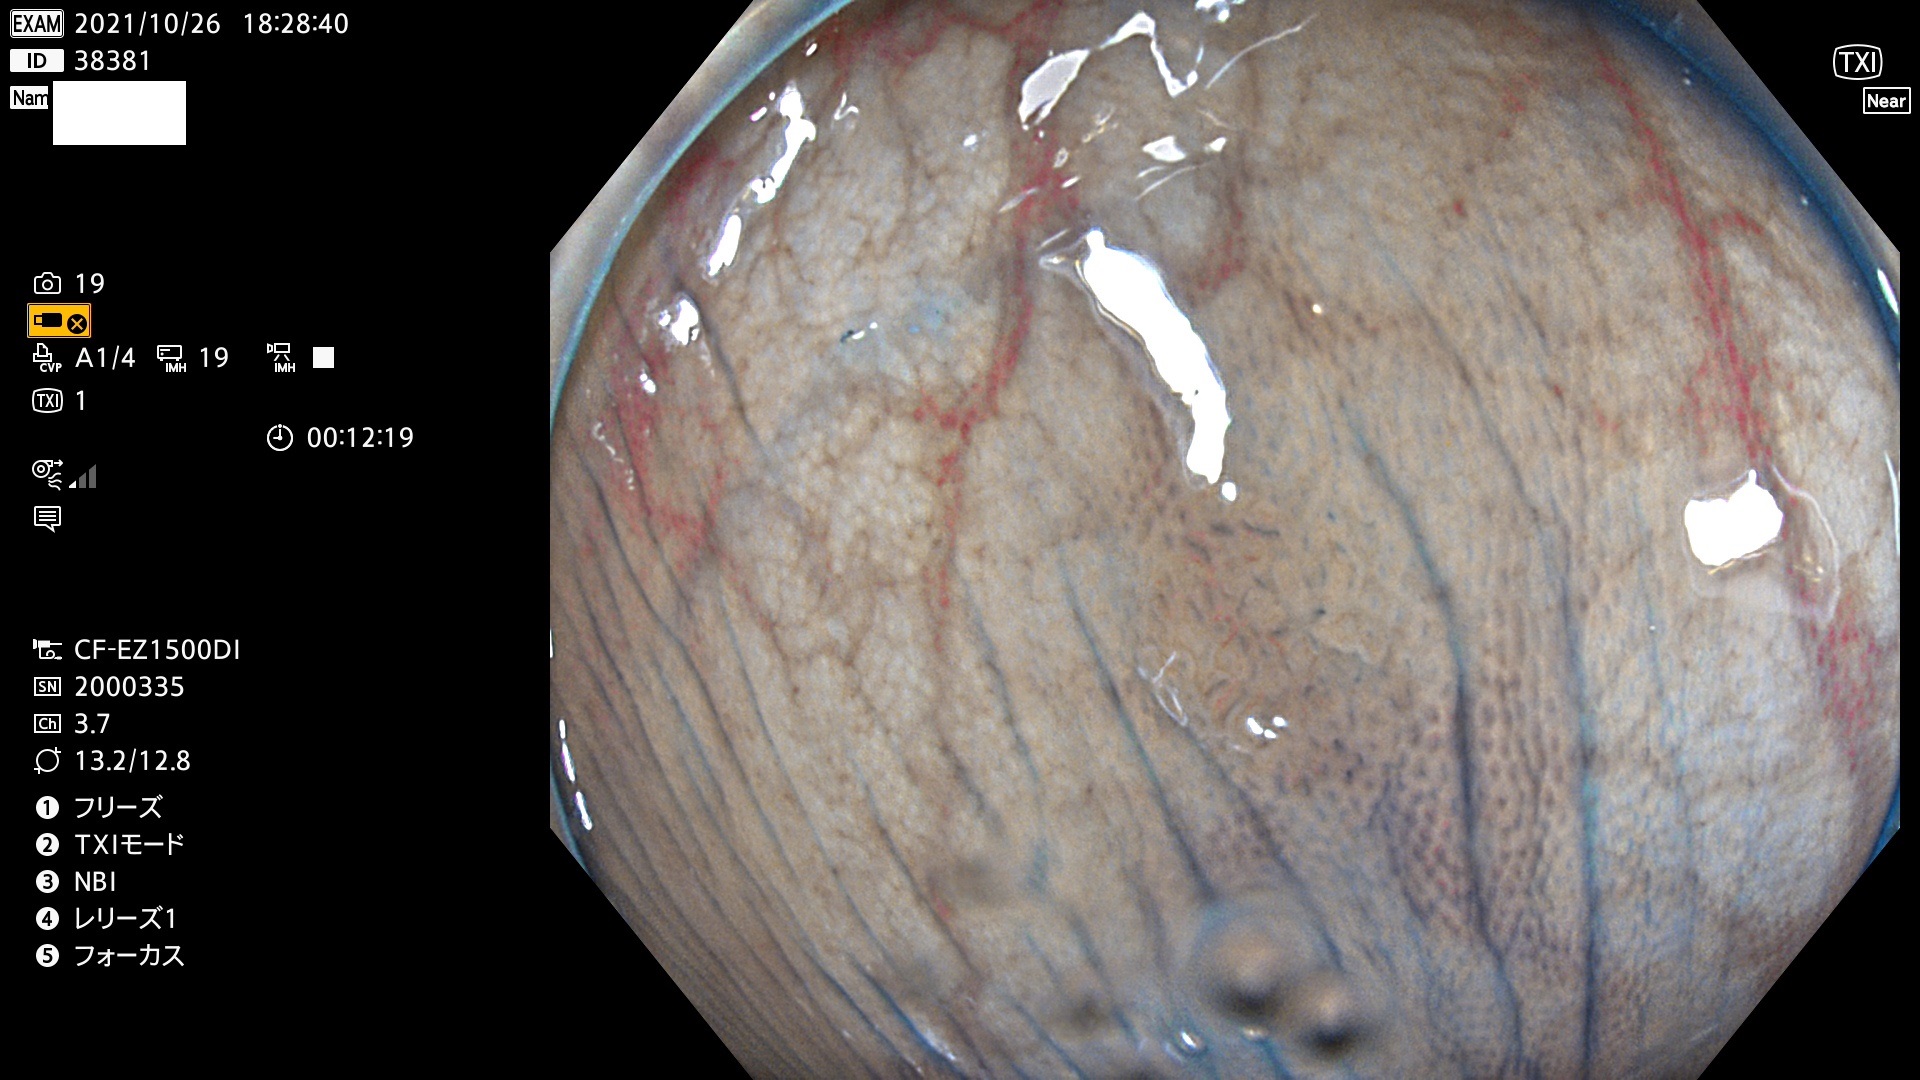

38300 38301 38302 38303 38304 38306 38307 38308 38309 38310 38311 38312 38313 38314 38315 38316 38317 38319 38321 38322 38323 38324 38325 38327 38331 38332 38333 38334 38337 38338 38339 38340 38341 38343 38346 38348 38349 38350 38351 38352 38353 38354 38355 38358 38359 38360 38361 38362 38363 38365 38366(SSAP) 38368 38369 38370 38371(SSAP) 38372 38374 38375 38376 38377 38378 38380 38381 38382 38383 38384 38385 38386 38388 38389 38391(SSAP) 38395 38397 38399

発見困難で危険性の高い平坦型病変(上記100名より抽出)